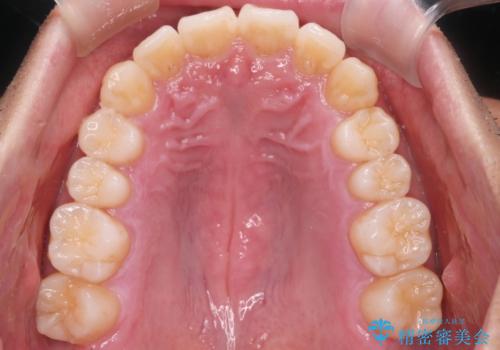

上の前歯が出ているという主訴が綺麗に改善されました。

その他の部位のがたつき、奥歯の噛み合わせも以前と比べると良くなっています。

目立たない装置で治療期間も10ヶ月と短く終了することができました。